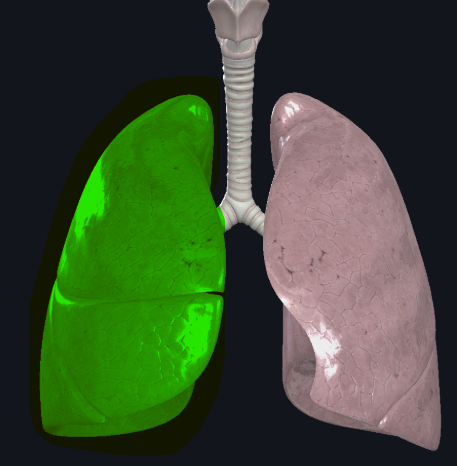

What structure is this?

Diaphragm

Cardiac Notch

What structure is this?

Superior lobe of the left lung

What structure is this?

Inferior lobe of the left lung

What structure is this?

Left lung

What structure is this?

Right lung

What structure is this?

Horizontal fissure of right lung

What structure is this?

Oblique fissure of right lung

What structure is this?

Oblique fissure of left lung